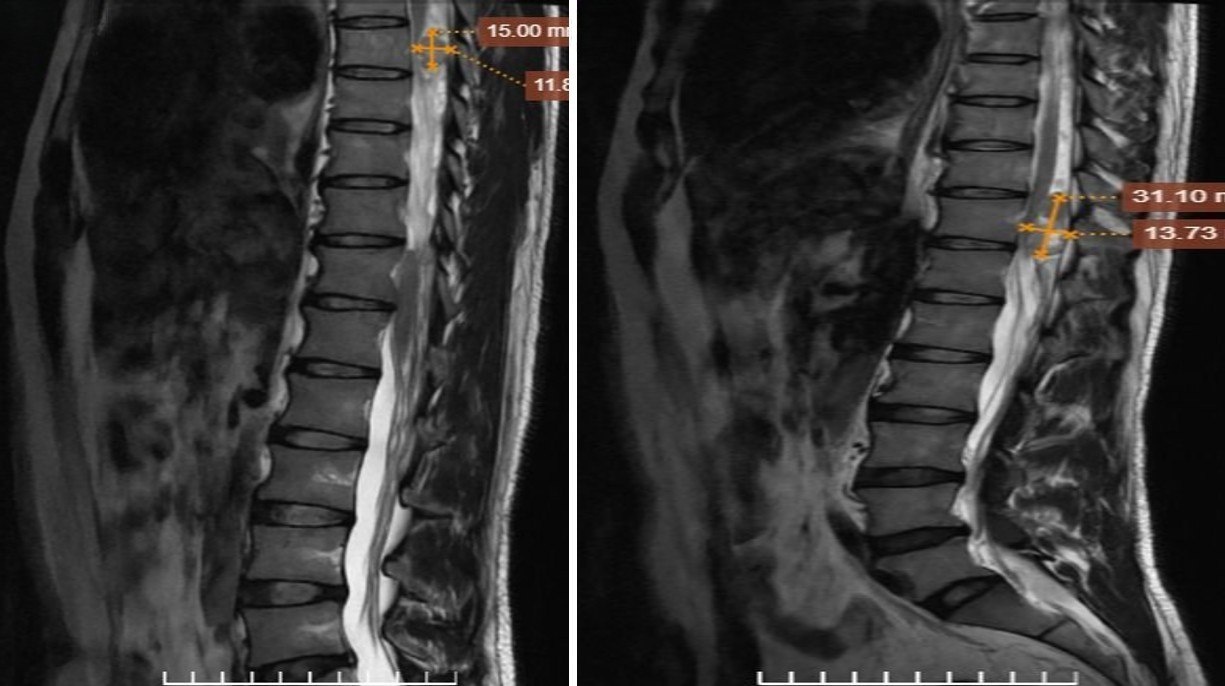

Để làm rõ chẩn đoán, bác sỹ chỉ định chụp cộng hưởng từ có tiêm thuốc đối quang từ. Kết quả ghi nhận các khối trong ống sống tại mức đốt sống ngực T7, T11 và một khối khu trú cạnh lỗ tiếp hợp bên phải mức L1/2. Các đặc điểm hình ảnh hướng đến chẩn đoán u bao dây thần kinh đa vị trí trong ống sống.

Trong chẩn đoán bệnh lý này, cộng hưởng từ được xem là phương tiện có giá trị cao nhờ khả năng phân giải mô mềm tốt. Phương pháp này giúp xác định chính xác vị trí khối u trong hay ngoài màng cứng, trong hay ngoài tủy sống, đồng thời đánh giá kích thước, số lượng và mức độ lan rộng của tổn thương.

Các đặc điểm hình ảnh điển hình như tín hiệu đẳng hoặc giảm nhẹ trên T1, tăng tín hiệu trên T2, ngấm thuốc mạnh sau tiêm gadolinium hay hình dạng “quả tạ” khi u lan qua lỗ tiếp hợp giúp định hướng chẩn đoán rõ ràng hơn.

Đặc biệt, cộng hưởng từ có tiêm thuốc đối quang từ đóng vai trò quan trọng trong việc phát hiện các tổn thương nhỏ hoặc nhiều ổ, từ đó giúp bác sĩ xây dựng chiến lược điều trị phù hợp.